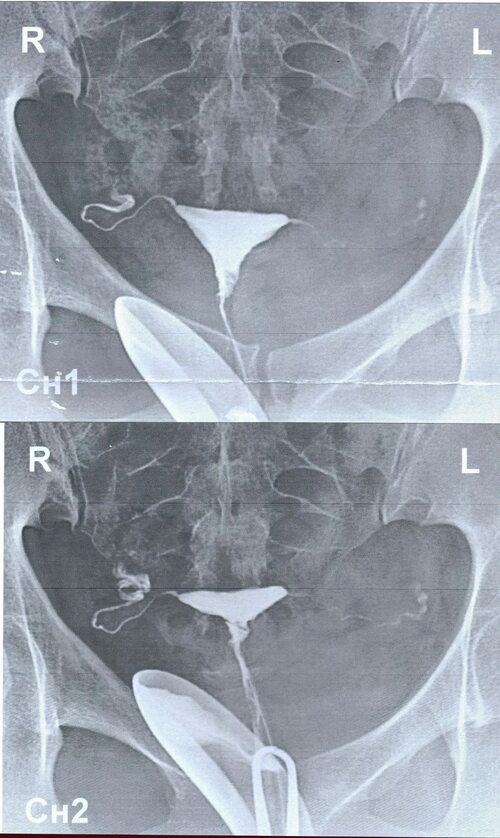

Фотографии маточных труб с наличием спаек

В этом разделе представлены фотографии, которые помогут вам визуально оценить состояние маточных труб и определить наличие спаек. Фотографии демонстрируют различные типы спаек, их расположение и возможные последствия для репродуктивного здоровья.